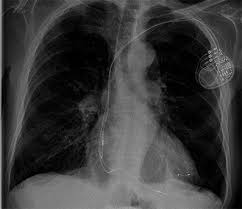

Implantationen Umm Universitatsmedizin Mannheim

Implantationen Umm Universitatsmedizin Mannheim from www.umm.de